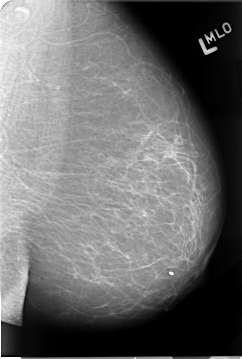

B_3067_1.LEFT_CC

LEFT_CC LINES 4632 PIXELS_PER_LINE 2848 BITS_PER_PIXEL 12 RESOLUTION 50 NON_OVERLAY